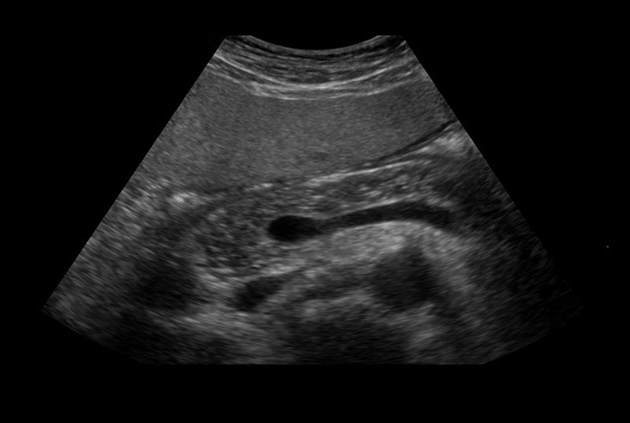

Superior guidance for all applications

Fujifilm Healthcare Americas is committed to designing tools that help surgeons navigate inside the human body and provide the necessary information to immediately make critical surgical decisions.

Fujifilm Healthcare's dedication to Surgeons provides outstanding ultrasound technology, professional support and the specialized tools necessary to best perform comprehensive real-time ultrasound imaging in Breast Surgery, General Surgery, Laparoscopic Surgery, Neurosurgery, Robotic Surgery and Surgical Oncology.

Recognized for our outstanding image quality, outstanding system reliability and intuitive use of cutting edge technology, Fujifilm Healthcare remains the standard in the field of Surgery.

Recognized for our outstanding image quality, outstanding system reliability and intuitive use of cutting edge technology, Fujifilm Healthcare remains the standard in the field of Surgery.